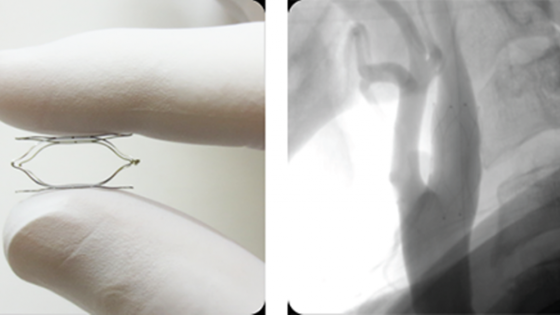

Этот изготовленный из титана прибора в виде бабочки может снизить риск инсульта после установки в шею. Устройство предложат группе пациентов, которым грозит повышенный риск острого нарушения мозгового кровообращения. Более полумиллиона жителей Великобритании могут пройти через операцию по установке крошечной титановой \"бабочки\" прямо в шею. Речь идёт о пациентах, страдающих от резистентной к лекарствам гипертонии, что существенно увеличивает риск инсультов, инфарктов и деменции. В ходе клинических исследований, проведенных в США, этот крошечный прибор, напоминающий клетку из проволоки, смог улучшить состояние здоровья у тех пациентов, которым упорно не помогали никакие лекарства от гипертонии. У некоторых из этих больных, которые принимали повышенные дозы таблеток без всякого эффекта, через несколько месяцев после установки устройства MobiusHD показатели артериального давления опустились до нормального уровня. Хотя пациентам всё равно надо принимать таблетки, теперь их дозы существенно уменьшились. В прошлом году MobiusHD одобрили в Европе, и теперь его будут предлагать пациентам из группы риска в самых разных странах. Девайс устанавливается в одну из сонных артерий - основных кровеносных сосудов, проходящих с обеих сторон шеи и снабжающих голову кровью. MobiusHD обеспечивает мягкое давление на нервы, регулирующие артериальное давление. Эти нервы, называемые барорецепторами, определяет изменения в давлении и посылают сигналы, чтобы мозг предпринимал необходимые меры. В обычных условиях, когда стенки артерий подвергаются напряжению из-за повышенного давления или гипертонии, барорецепторы отправляют сигналы в мозг, ритм сердца изменяется, кровеносные сосуды расширяются или сужаются, и давление приходит в норму. Но у имеющих резистентность к лекарствам от гипертонии пациентов барорецепторы менее эффективны. Новый гаджет оказывает дополнительное стимулирование нервов, и мозг считает, что артериальное давление постоянно повышено. Он посылает сигнал снижать ритм сердца и расширять кровеносные сосуды, что и переустанавливает всю систему.